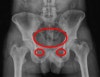

골반뼈 영상에서는 3개의 원이 보입니다. 1개은 골반 가지(pelvic brim)에 의해서 생기고 2개는 폐쇄구멍(obturator forament)을 말합니다. 골반뼈의 테두리를 따라서 선을 그려보면 정상적으로 부드러운 연결선을 보이게 되고 이는 아주 나이가 많은 사람이라 하더라도 SI joint와 Symphysis pubis에서도 끊어지지 않습니다.

골절이 발견된다면 반드시 다른 곳에 끊어지는 부위가 있는지 확인해야 하는데, 대부분의 경우에 다른 곳에 골절이나 분리가 있기 때문입니다.